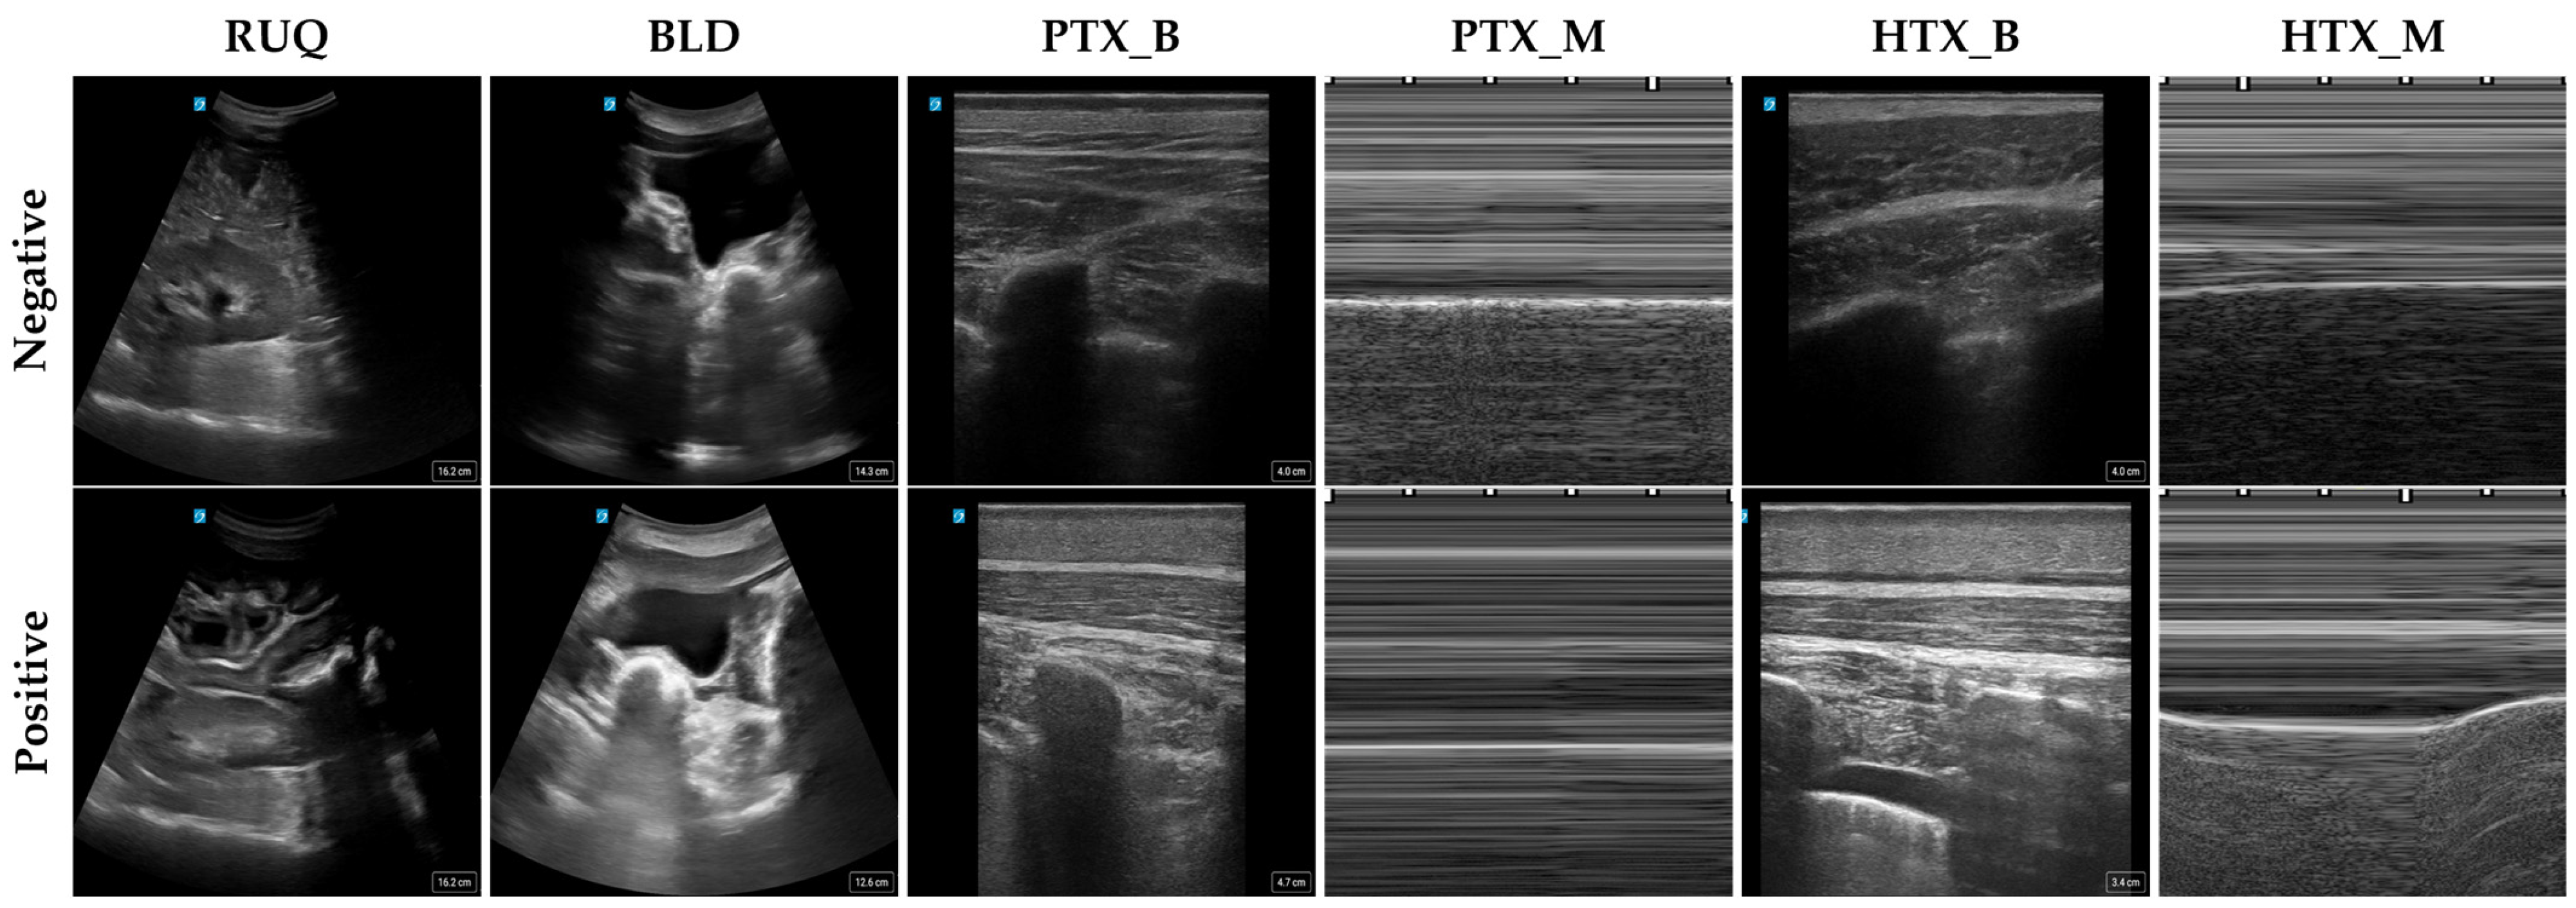

| Scan Point | RUQ | BLD | PTX_B | PTX_M | HTX_B | HTX_M |

|---|---|---|---|---|---|---|

| Positive Images | 30,000 | 20,845 | 34,957 | 4525 | 76,431 | 9368 |

| Negative Images | 31,396 | 22,049 | 54,420 | 6425 | 54,420 | 6425 |

| Total Number of Images | 61,396 | 42,894 | 89,377 | 10,950 | 130,851 | 15,793 |

| Subjects | 25 | 21 | 22 | 20 | 25 | 25 |